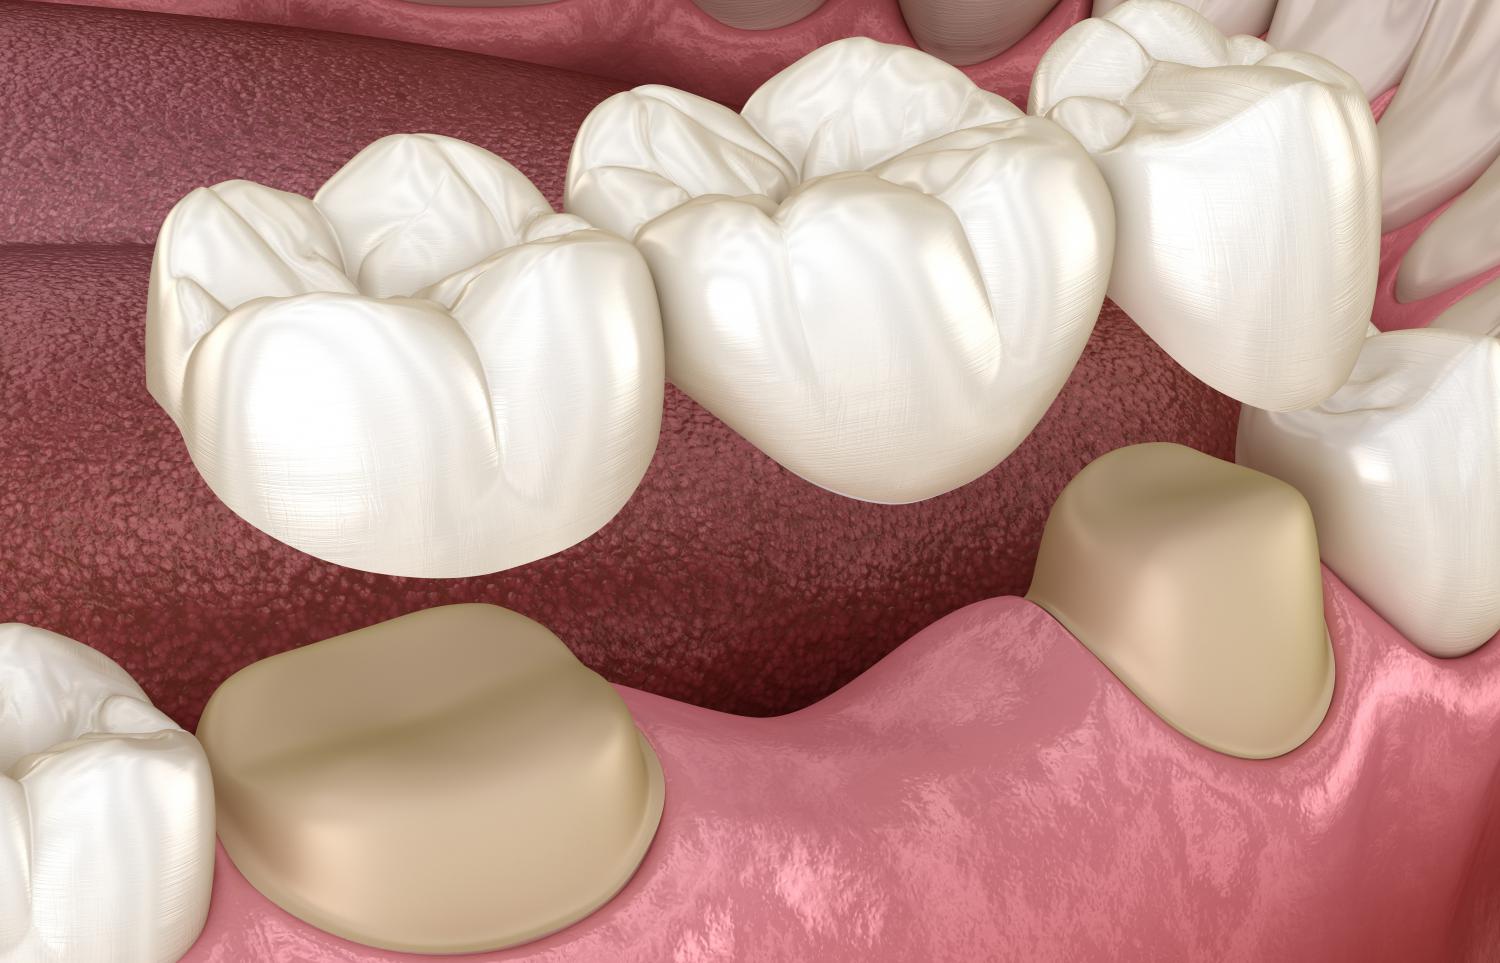

Стоматология: коронки и мостовидные протезы